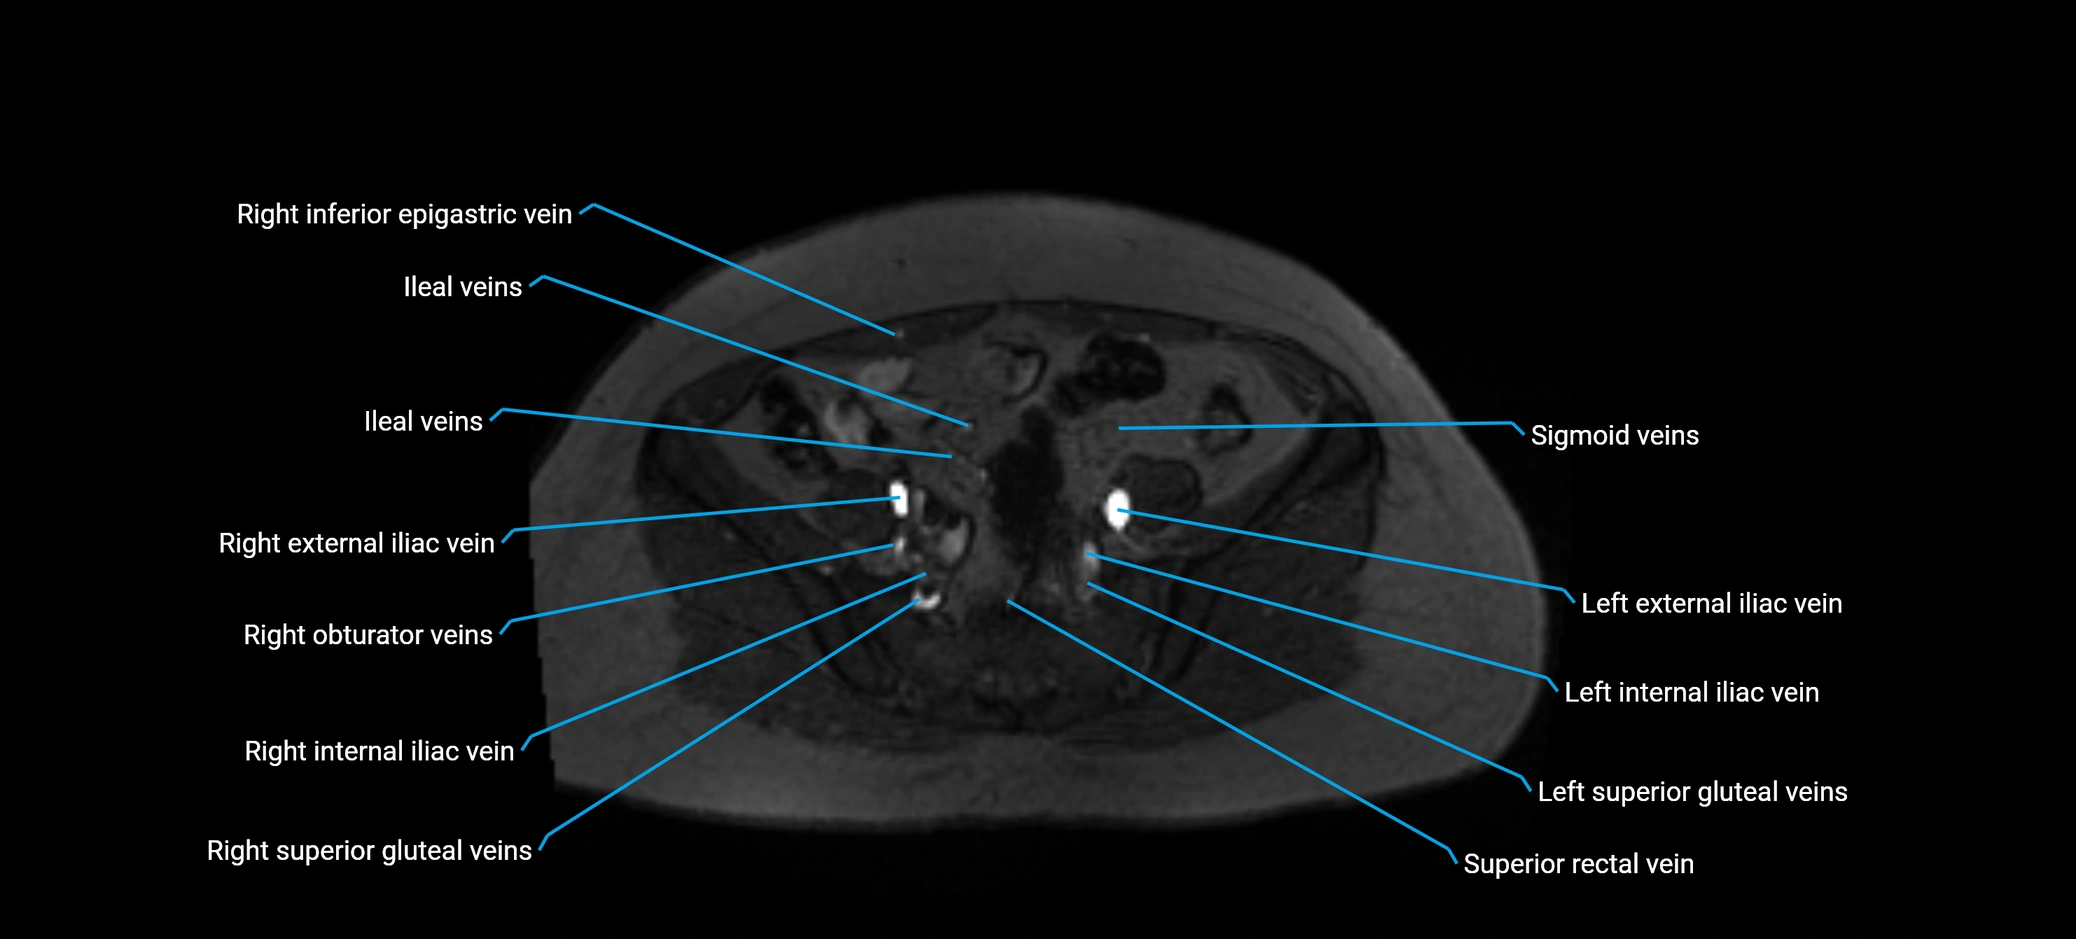

MRI image

image